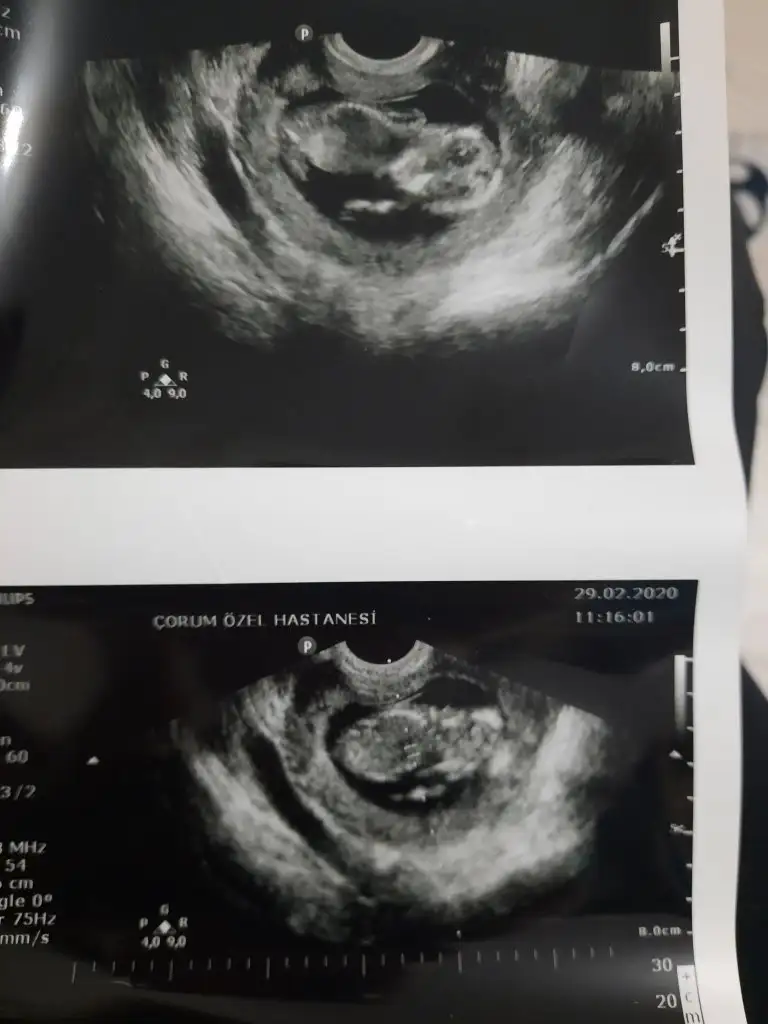

dr soylemeden siz gorun genital nub teorisi ( bebegin cinsiyeti)

iyi akşamlar kızlar bizede bir tahmin Varmı 12+6 haftalığız burada

Senin nubu çizdim cnm arkadaşında çizdim pipide vardı arkadaş pipi olsa söylemezmi deyince bende diğer 10 ve 11 haftasndaki tahminim devam dedim çok istiyordu pipiyi dr görmedi deyince ne kadar geç ögrenise dedim yoksa baya baya pipiydi çizdiğim usg 😊 seninkinide çizdim parelel görünüyor tabi pozisyonu nubu bazen değiştiyor. umarım 31 yanlış tahminim var arasında olmazsın onlar beni yanıtan usgler 😊